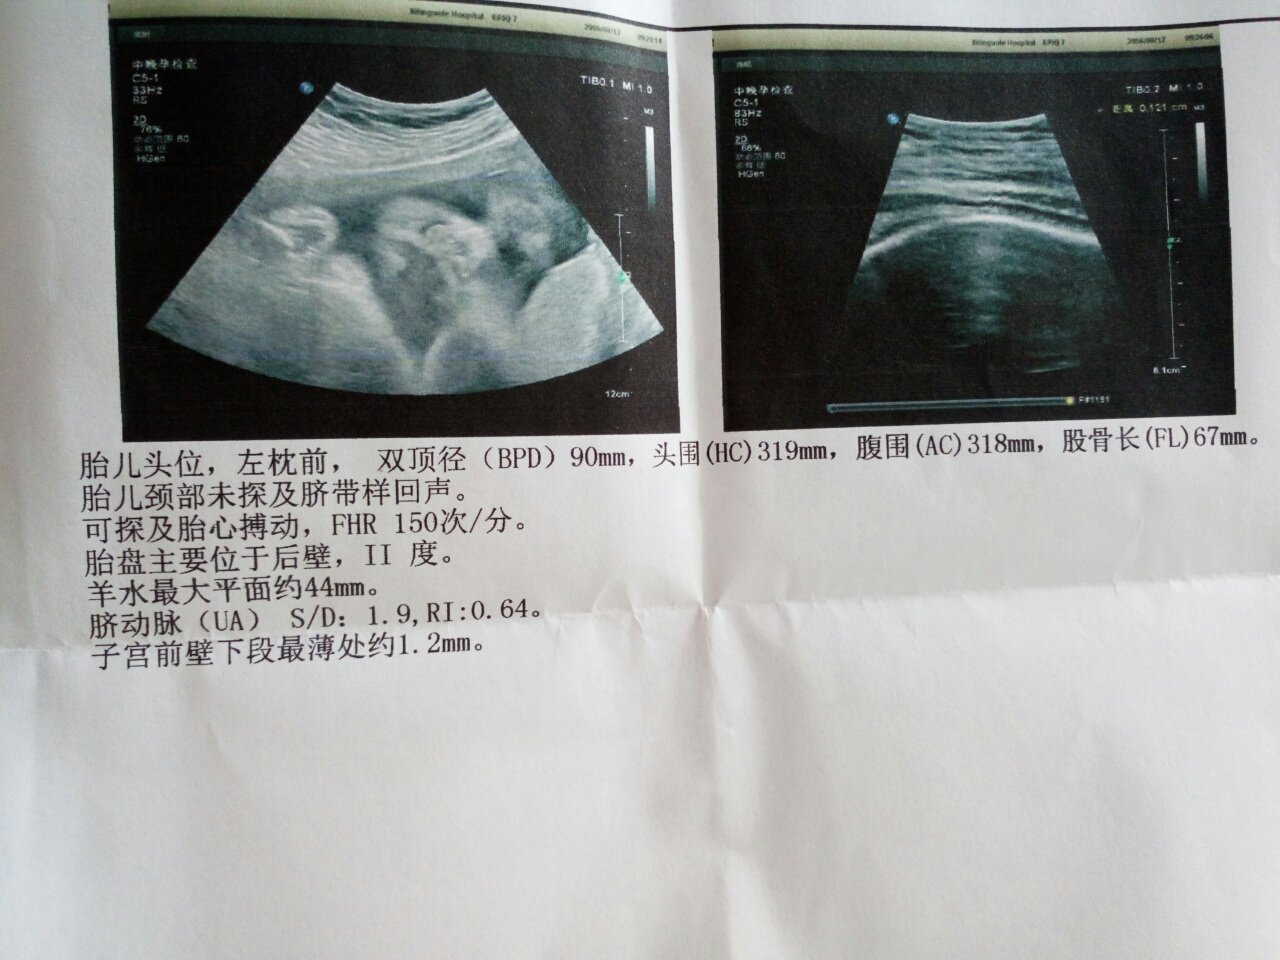

母亲子宫最薄处1.2mm,大夫建议现在刨妇产 胎儿此时刨妇产算早产吗? 母亲子宫最薄处1.2mm,大夫建议现在刨妇产。胎儿此时刨妇产算早产吗? 点击展开 136*****018_gqQt 2016-08-17 12:59 为您推荐: 其他回答 那就听医生的近快 150*****766_kv7p 2016-08-17 21:53 听接诊医生的吧。 莫如尽 2016-08-17 16:18 肯定不如足月儿,出生之后听医生的,该住院治疗就住院治疗。 莫如尽 2016-08-17 15:55 医生是怎么说的 150*****766_kv7p 2016-08-17 14:44 早点,,,,, 霸道宝宝 2016-08-17 14:41 加载更多 相关问题 孩子早产刨妇产 8个月就出生了 预产期是2-10我想1-29刨妇产,a算早产吗?求解 早产的宝妈都是顺产还是破妇产